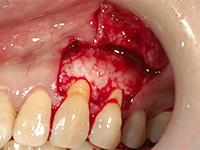

結合組織移植術

右上3番、4番の歯の根が露出していたため、上顎の裏側から結合組織を移植しました。

上顎裏側の結合組織を摘出しています。術後の傷も、きれいに治りました。